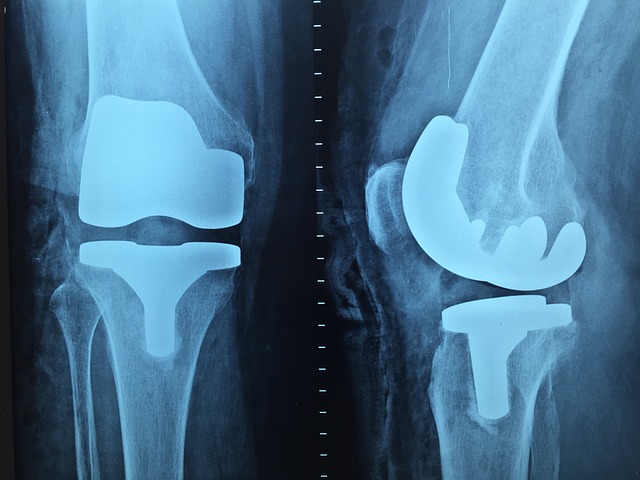

- 인공관절 치환술 – 심한 관절염의 경우 손상된 관절을 인공관절로 교체.

무릎 인공관절 수술 회복기간과 수술비용 알아보기(+지원사업)

무릎 인공관절 수술은 관절염, 외상, 퇴행성 질환 등으로 인해 손상된 무릎 관절을 인공관절로 대체하는 수술입니다. 이 수술은 통증을 완화하고 무릎의 기능을 개선하여 일상생활의 질을 높이